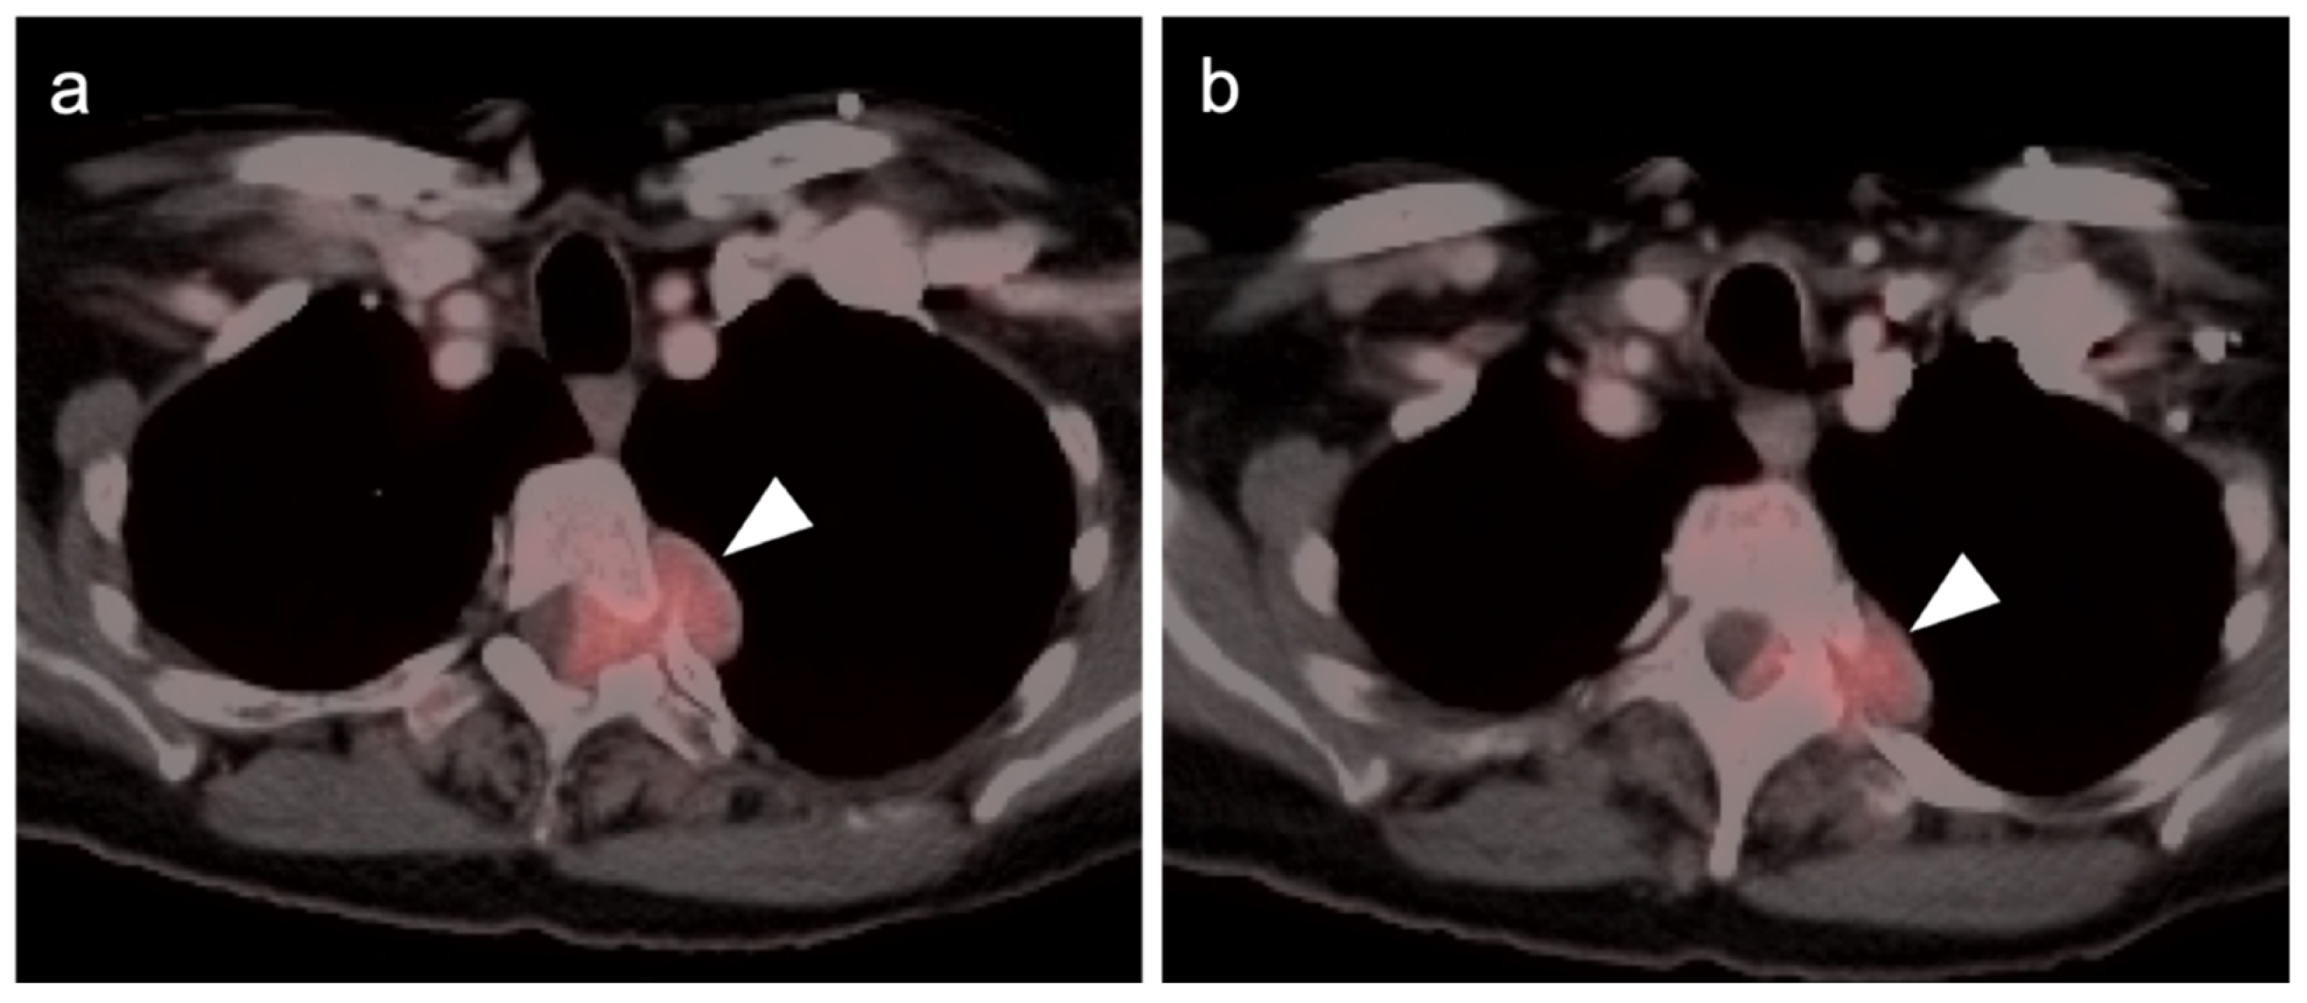

- Qiu, S.; Zou, S.; Cheng, S.; Song, S.; Zhu, X. Positive FAPI PET/CT in a Bilateral Mammary Angiosarcoma Patient with Less Impressive FDG PET/CT Images. Clin. Nucl. Med. 2022. [Google Scholar] [CrossRef]

- Camoni, L.; Albano, D. Contrast-enhanced 18F-FDG PET/CT to differentiate primary cardiac lymphoma from primary cardiac angiosarcoma. J. Nucl. Cardiol. 2021, 1–3. [Google Scholar] [CrossRef]